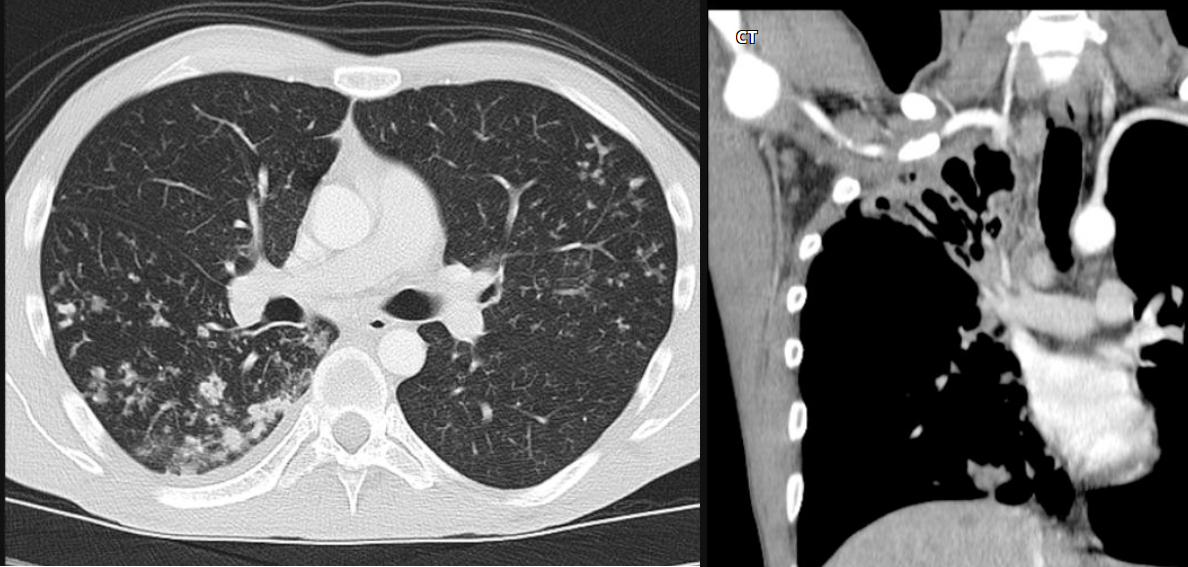

80 Mulher, Tosse

Consolidação com cavitação em lobo superior direito

Adenocarcinoma

Consolidação em lobo superior direito com áreas de cavitação

Padrão de micronódulos centrolobulares com árvore em brotamento

TB pós primária.